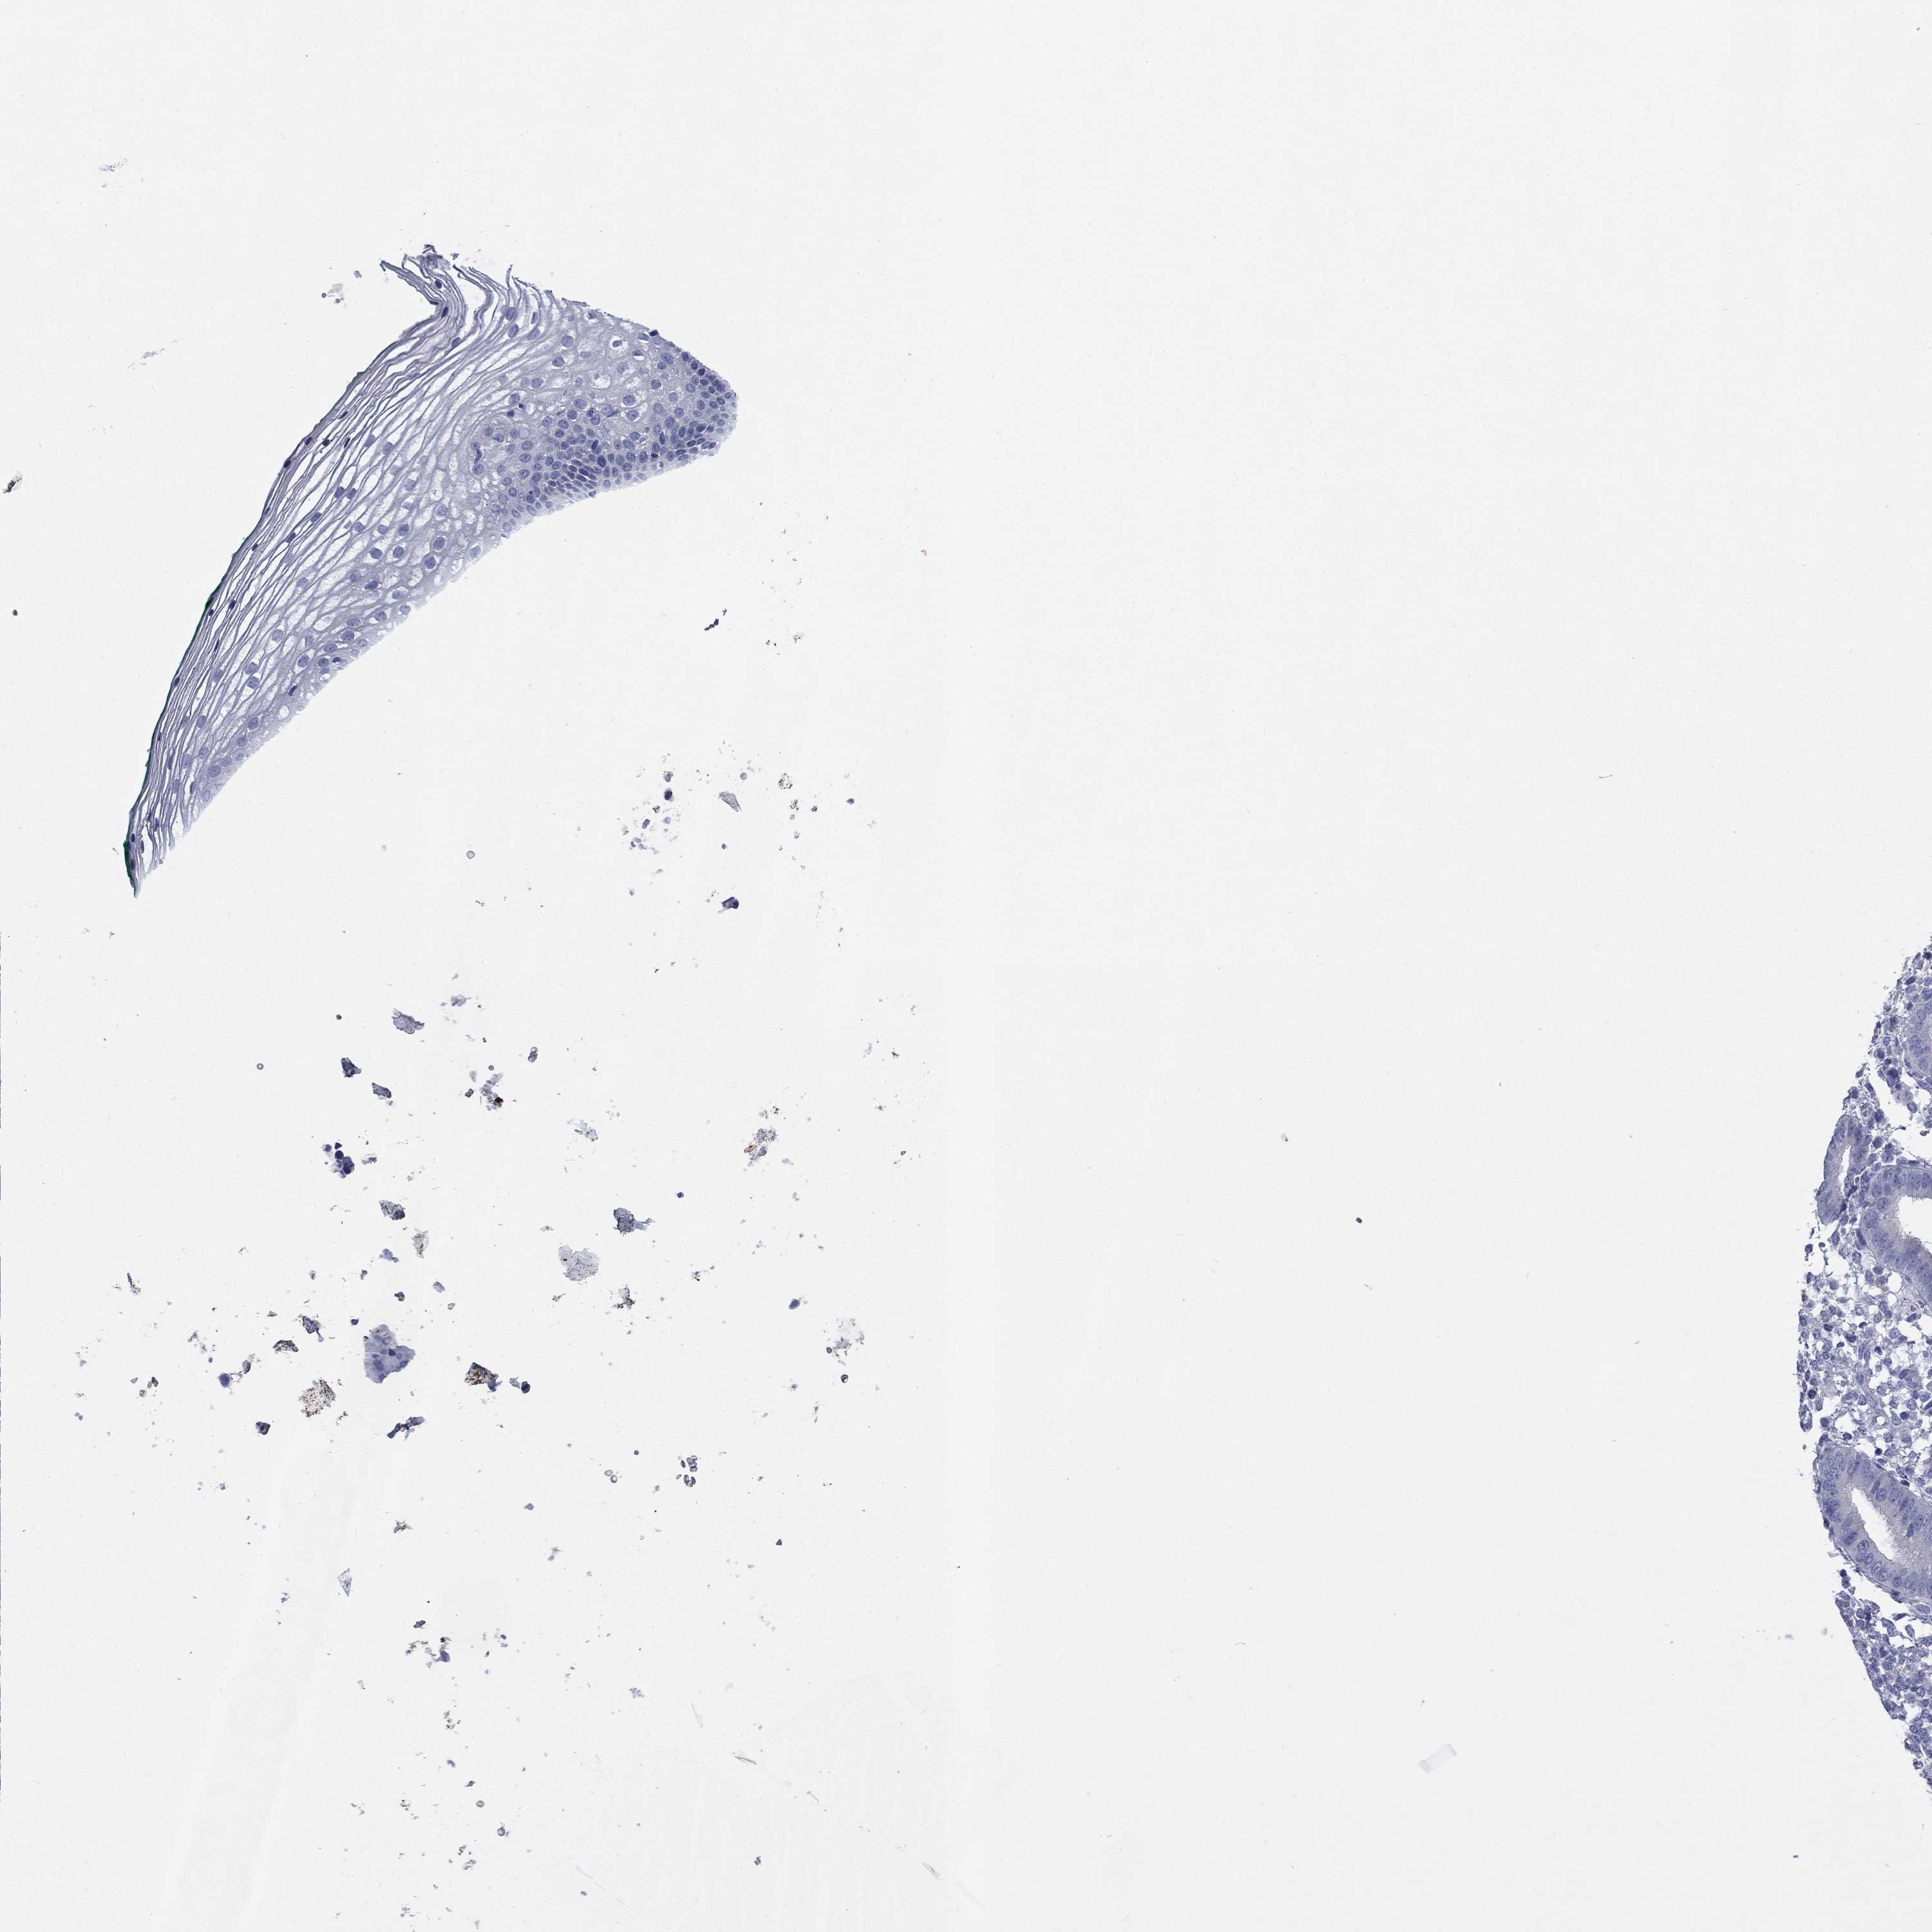

FCER2